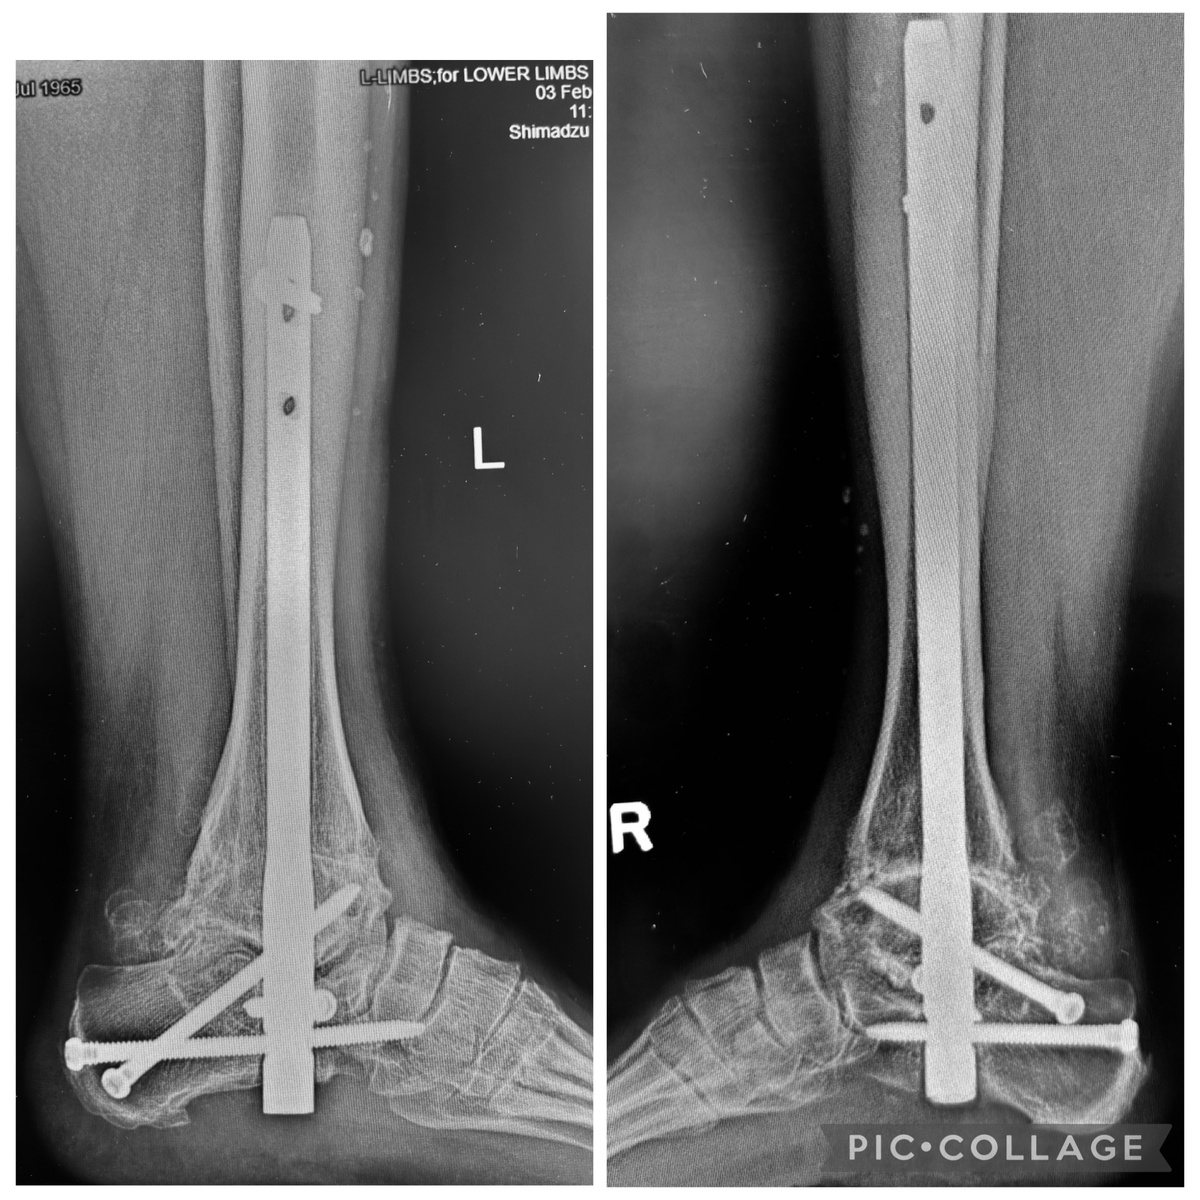

Здесь я показываю пример, когда у женщины 60 лет 3,5 года назад я сделал артродез сразу и голеностопного, и подтаранного суставов, ибо оба были разрушены. Год назад она пришла со второй стопой. Там ситуация была чуть получше, но спасать всё равно было нечего, поэтому - аналогичная операция, для симметрии.

Прошёл год после второй операции, результат налицо. Продолжает работать в библиотеке, никаких болей нет, вообще не ограничена ни в быту, ни в активности.

Не так страшен чёрт, как его малюют ))) Хотя рентген выглядит угрожающе, конечно )))